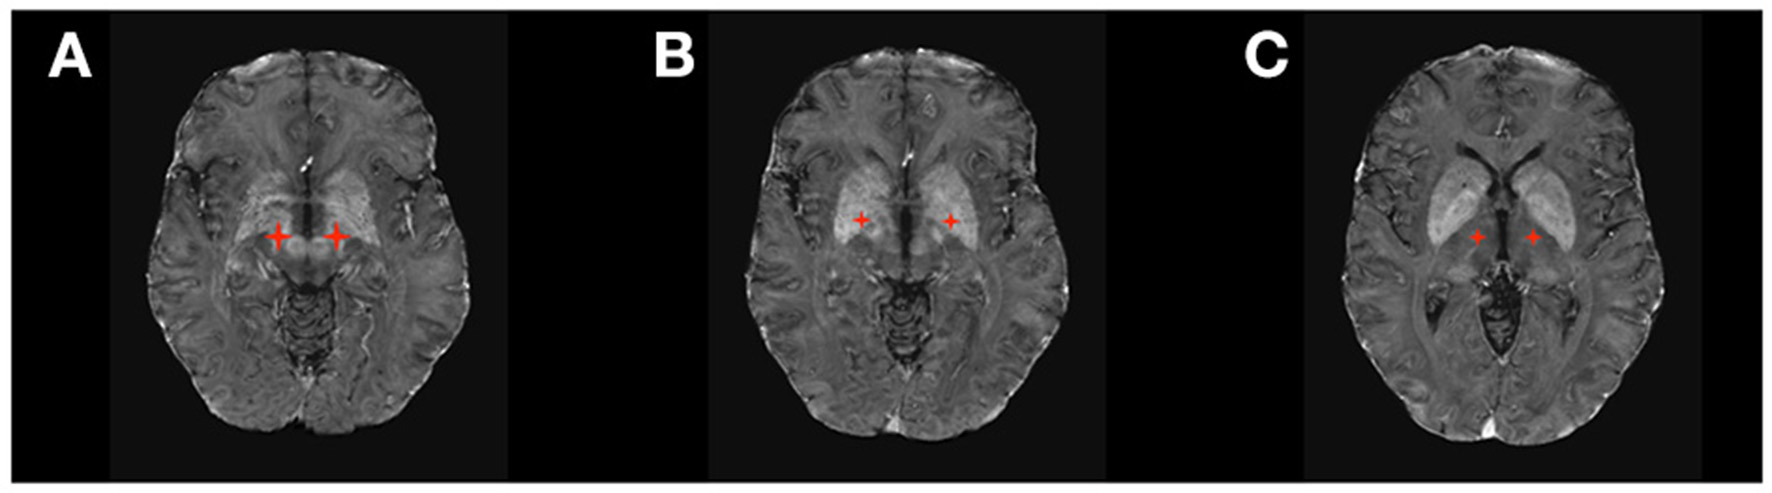

Figure 1

DBS targets in Movement Disorders. (A) Subthalamic Nucleus (STN); (B) Ventral Intermediate Thalamic Nucleus (VIM); (C) Globus Pallidus Pars Interna (GPi).

DBS received FDA approval in 2018 for the treatment of DRE based on evidence from the SANTE Trial (21, 22), a double-blinded randomized clinical trial of bilateral stimulation of anterior nucleus of the thalamus (ANT) for DRE (Figure 2). This study showed a 40% seizure frequency reduction in the stimulated group compared with 14.5% in the control group at 3 months. Encouragingly, DBS of the ANT, as observed in other indications, also shows progressive improvement in effect over time. In the unblinded phase of SANTE trial participants, there was 69% median seizure frequency reduction at 5 years (22). Consistent with ANT location within the medial limbic circuit, the best seizure control effect of stimulation was seen for temporal lobe epilepsy (76% improvement) compared to epilepsies of the frontal lobes (59%) or other locations (68%).

DBS targets in Epilepsy. (A) Anterior Thalamic Nucleus (ANT); (B) Centromedian Thalamic Nucleus (CM); (C) Hippocampus.

The efficacy of DBS of other brain structures to treat epilepsy remains inconclusive due to the lack of large randomized clinical trials (RCT). Stimulation of the hippocampus has been investigated as a treatment for medial temporal lobe DRE not amenable for resection and has shown positive evidence of seizure reduction by 26–40% in small RCTs (23–27) and up to 95% in smaller non-randomized trials (20). The largest RCT for DBS of the hippocampus (16 patients) showed that seven out of eight patients in the active therapy group had a reduction >50% in seizure frequency, and four of them became seizure-free (23). DBS to the centromedian nucleus of the thalamus (CMT) has also been studied, as the CMT projects widely to many cortical regions, especially frontal lobes (20, 28). Evidence from several small RCTs shows a better response to DBS of CMT in generalized epilepsy than focal epilepsy (27, 29).